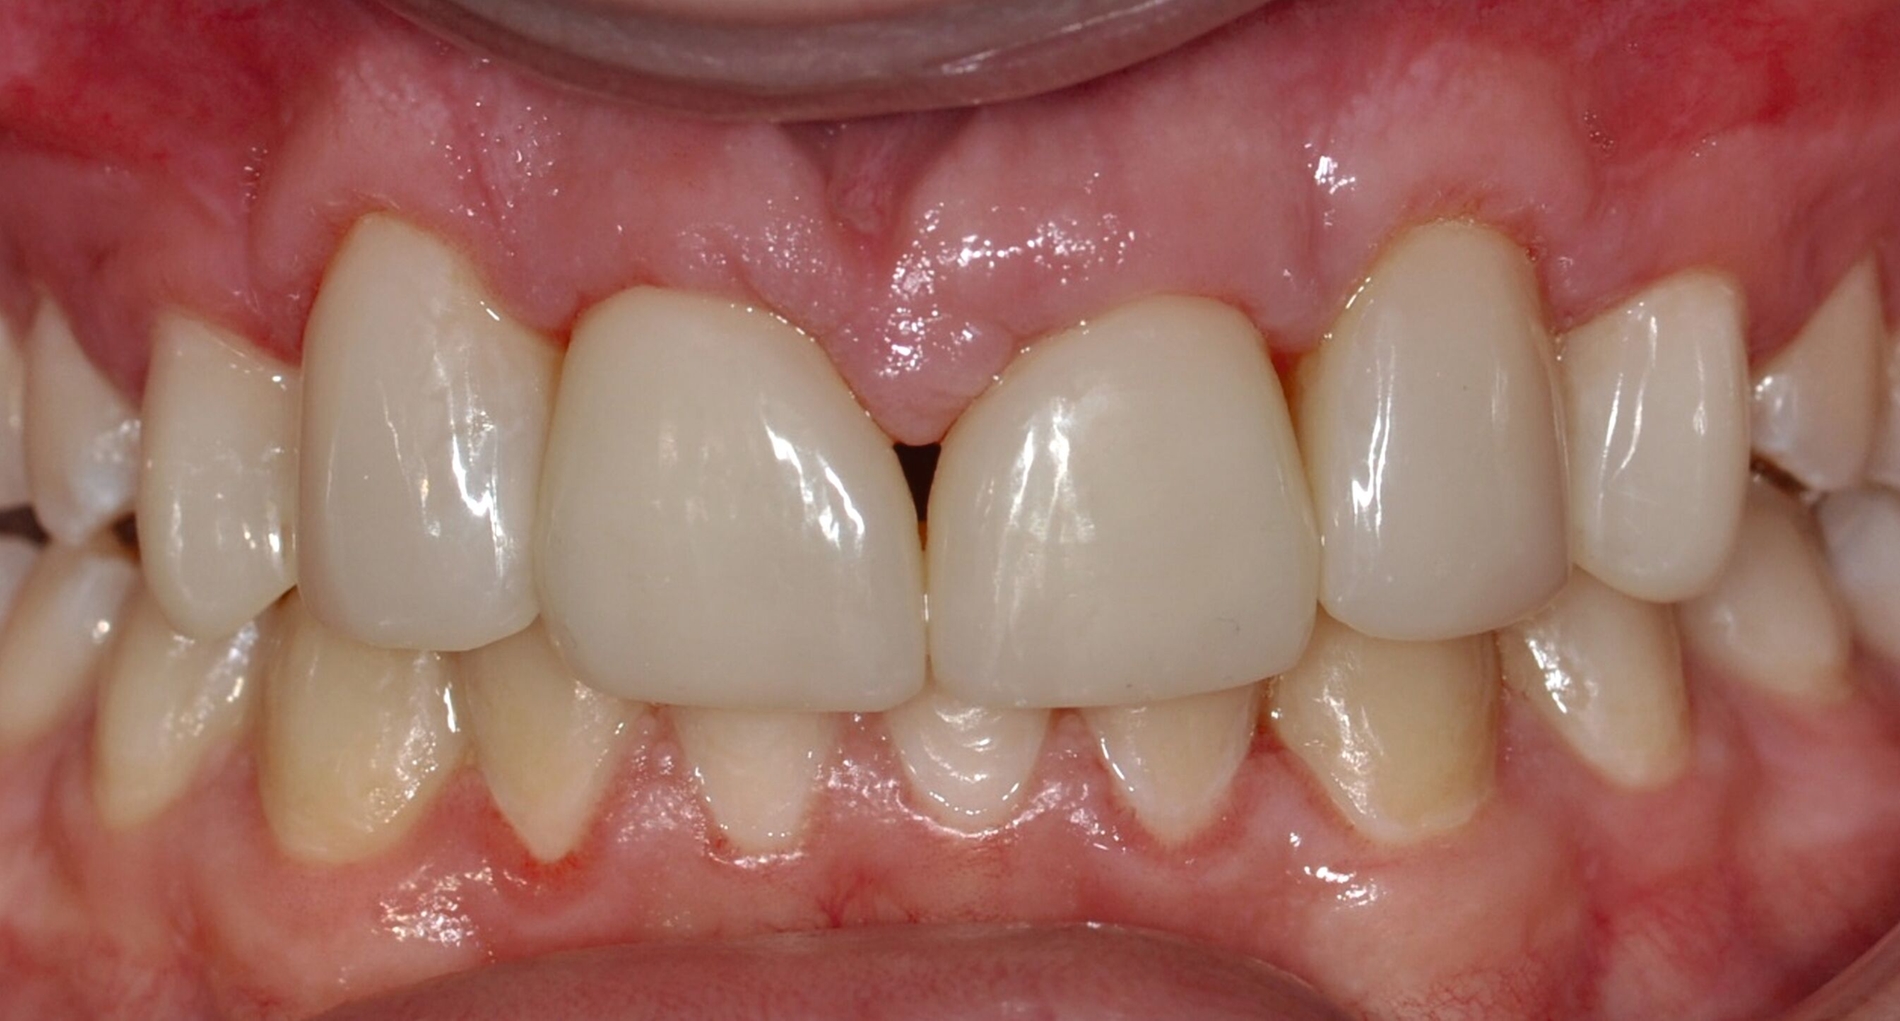

Anschließend werden laborgefertigte Non-prep-Kompositveneers aus dem gleichen Material für die Zähne 12 und 22 hergestellt. Diese werden in einer zweiten Sitzung nach dem Abstrahlen des Zahnschmelzes beziehungsweise der Restaurationsinnenflächen mit Al₂O₃-Pulver und dem Einbringen von Retraktionsfäden adhäsiv (IPS Empress Direct & Flow A2) eingesetzt. Zur Optimierung der Papillenästhetik wird der breite mediale Papillenbereich vor dem Einsetzen der Veneers durch eine externe Gingivektomie reduziert. Der marginale Gingivaverlauf der Zähne 12 und 22 wird unter Berücksichtigung der Lachlinie und in Absprache mit dem Patienten nicht nach apikal auf das Niveau der Eckzähne verlagert. Zusätzlich werden die Zähne 14 und 24 im Bereich der bukkalen Höckerspitzen direkt mit Komposit umgeformt und harmonisch an die neue Frontzahnsituation angepasst.

Die direkten und indirekten Kompositrestaurationen werden abschließend mit Skalpellen (Nr. 12), diamantierten Schallspitzen, rotierenden Instrumenten und Soflex-Scheiben ausgearbeitet, in statischer und dynamischer Okklusion kontrolliert, entsprechend eingeschliffen und auf Hochglanz poliert. Die Hygienefähigkeit der marginalen Bereiche wird sichergestellt und dem Patienten werden zur häuslichen Reinigung der Zahnzwischenräume passende Interdentalraumbürstchen angepasst (Abbildung 3).